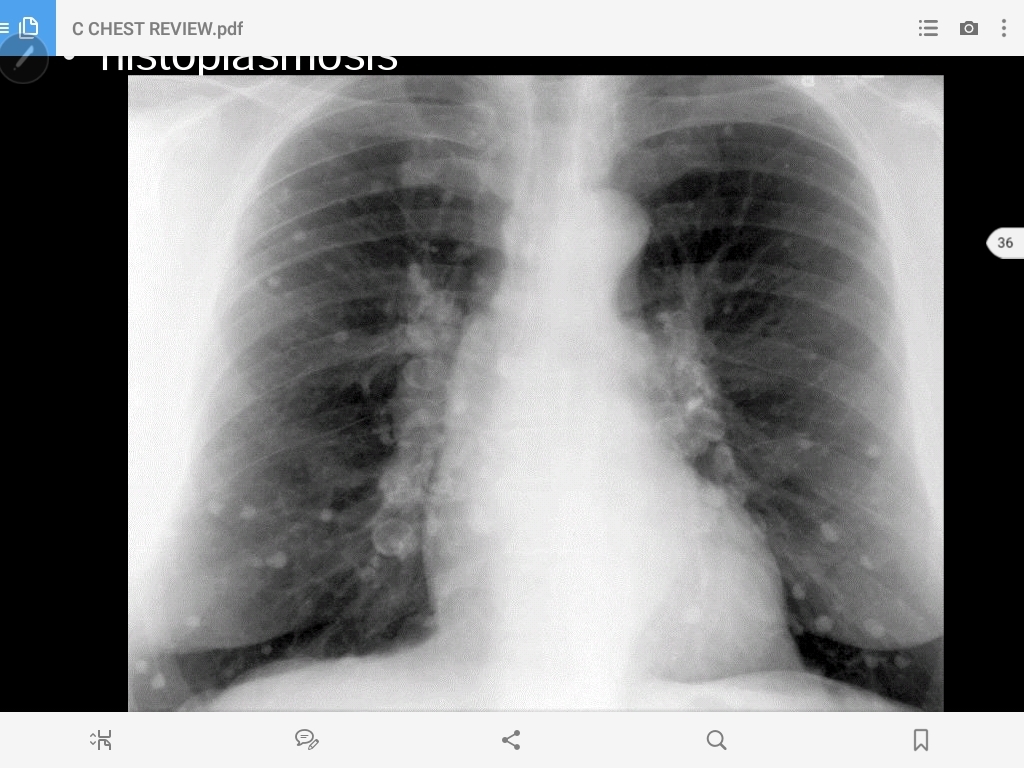

histoplasmosis

hilar lymph node enlargement and a peripheral granuloma (Ranke complex)